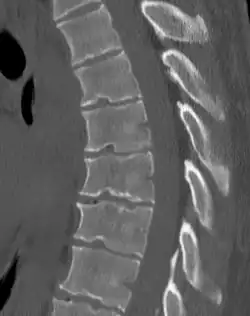

Scheuermann's disease

Other names | Scheuermann's kyphosis, Calvé disease, idiopathic juvenile kyphosis of the spine |

Scheuermann's disease on lateral Xray of the T spine | |

Scheuermann's disease is a skeletal disorder.[3] It describes a condition where the vertebrae grow unevenly with respect to the sagittal plane; that is, the posterior angle is often greater than the anterior. This uneven growth results in the signature "wedging" shape of the vertebrae, causing kyphosis. It is named after Danish surgeon Holger Scheuermann.[4][5][6]

Diagnosis is typically by medical imaging. The degree of kyphosis can be measured by Cobb's angle and sagittal balance.